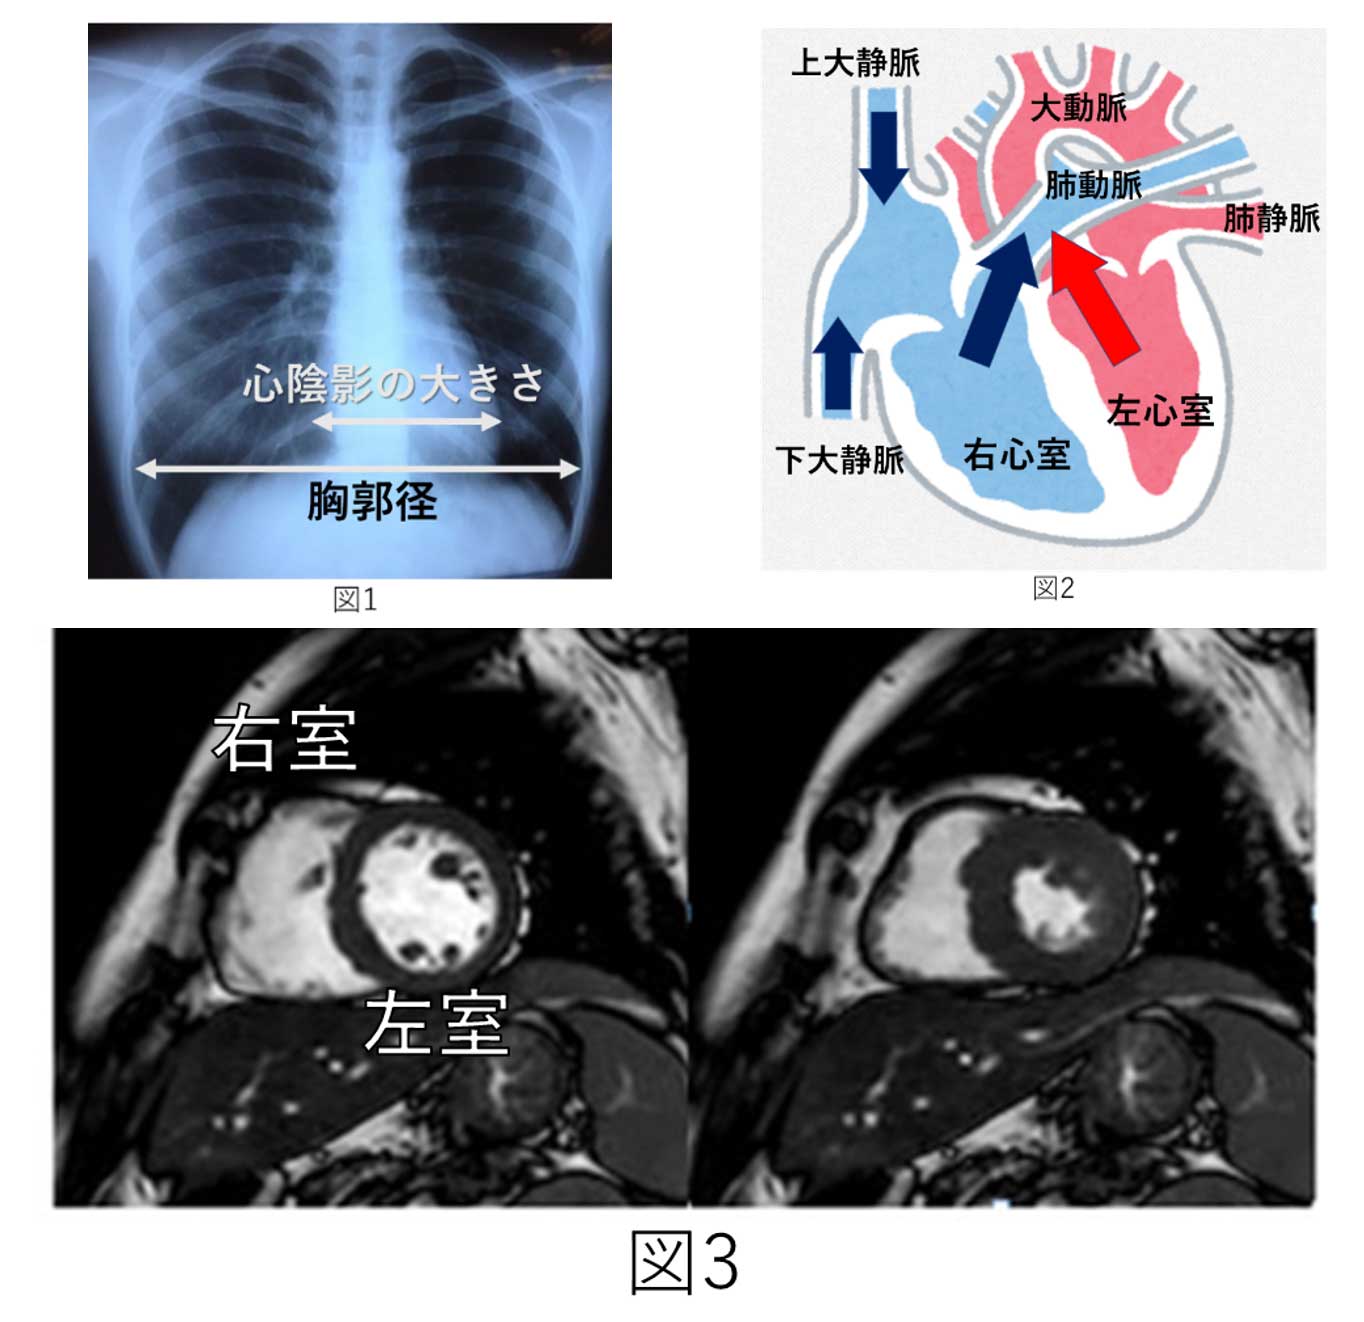

我々、小児科医が日々診療している中で、胸部X線撮影を行うと、下図1のように胸の幅に対する心陰影の幅(心胸郭比と言います)が小さい「小心臓」を時折、見かけます。

心胸郭比が42%未満のことを「小心臓」と定義していますが、「小心臓」を有する児の中に、頭痛・めまい・立ちくらみなどの循環器症状を共通して認めることがしばしばあり、「小心臓症候群」と呼ばれています。

小心臓症候群に関する過去の研究では、心臓が小さいことにより、左心室から全身に送られる血液量が少ないこと(低心拍出状態)が症状の原因であると、考察されています。

今回、我々は、これまでの研究が心臓超音波検査を用いた研究であったのとは異なり、心臓MRIを用いて、心臓を立体的に評価することで、より詳細な解明を行いました。(下図3)

これまでの研究結果と同様に、全身に送られる血液量が少ないことが分かりました。また、それと同時に、右心室から肺に送られる血液量が少ないことや、症状の重症度には右心室の収縮力が関与している可能性が新しく示唆されました。